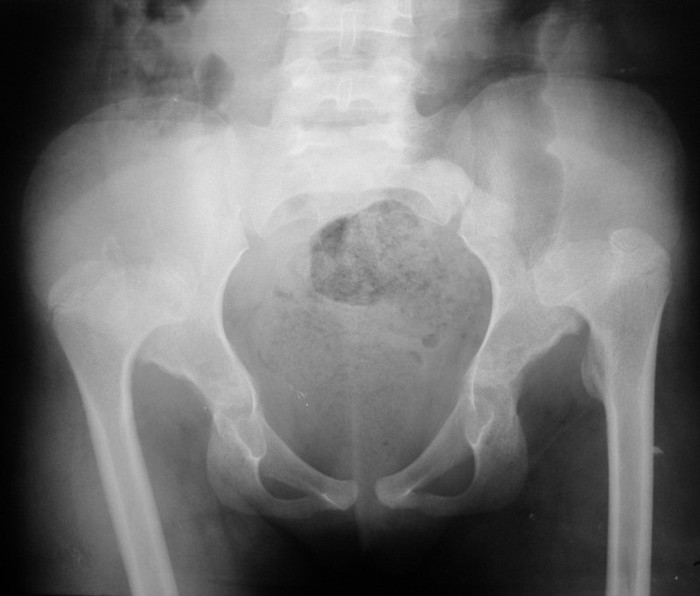

Уважаемые коллеги!Окажите, пожалуйста, консультативную помощь в данном случае. Девочка, 10 лет. Жалобы: на «утиную » походку, хромоту при ходьбе. Анамнез заболевания: болеет с рождения. Ребенок находится на полном государственном обеспечении, ребенок находится в Часов-Ярской школе интернате для детей сирот. Ранее не лечилась. Наблюдалась у травматолога, была прописана ортопедическая обувь, ортопедический режим. Год назад переведена в школу-интернат, где и находится до сих пор. Место болезни: кожные покровы обычной окраски, без видимых повреждений. У ребенка «утиная» походка. При осмотре укорочение левой ноги общее 1 см. Объем движений в т\б суставах: сгибание-разгибание: слева и справа - 80°- 150°; приведение-отведение: слева и справа - 70°-115°; ротация внутрь-наружу: слева - 10°-10°, справа - отсутсnвует-10°. На рентгенограммах от 14.10.10. таза отмечается вывих обеих бедренных костей кверху с образованием неоартрозов на уровне крыш подвздошных костей. Вертлужные впадины мелкие, запустевшие. Крыши скошены. Головки бедренных костей грибовидной формы, шейки укорочены, широкие – врожденный вывих обеих бедер. Тактика лечения? Заранее благодарим!